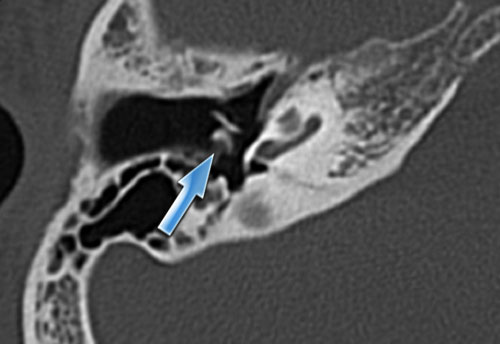

Bên trái là hình ảnh của một bệnh nhân khác với xương chũm xơ cứng.

Ống đá chũm được nhìn thấy rõ ràng.

Nếu bệnh nhân này là nạn nhân chấn thương, ống này có thể dễ dàng bị nhầm lẫn với đường gãy xương (mũi tên).